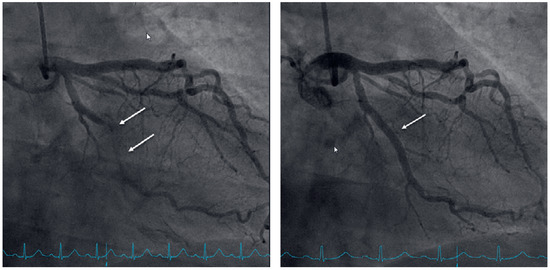

Myocardial infarction with nonobstructive coronary arteries (MINOCA): Myocardial infarction (MI) with non-obstructive coronary arteries (MINOCA) is defined as MI according to the fourth universal definition of MI [1] without coronary stenosis ≥50% on...